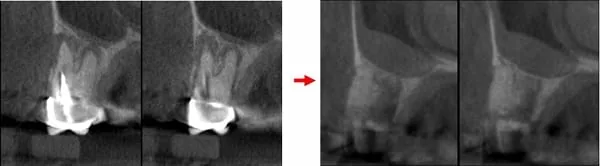

治療前:第一小臼齒發炎導致外側骨破洞 → 治療後:拔除後窩洞填入骨粉及膠原蛋白

治療前:第5顆缺牙處,骨高度約2mm → 治療後:鼻竇增高至10mm

治療前:第6顆缺牙處,骨高度約1mm → 治療後:鼻竇增高至9-12mm

治療前:鼻竇非常低 → 治療後:墊高鼻竇,填入大量骨粉